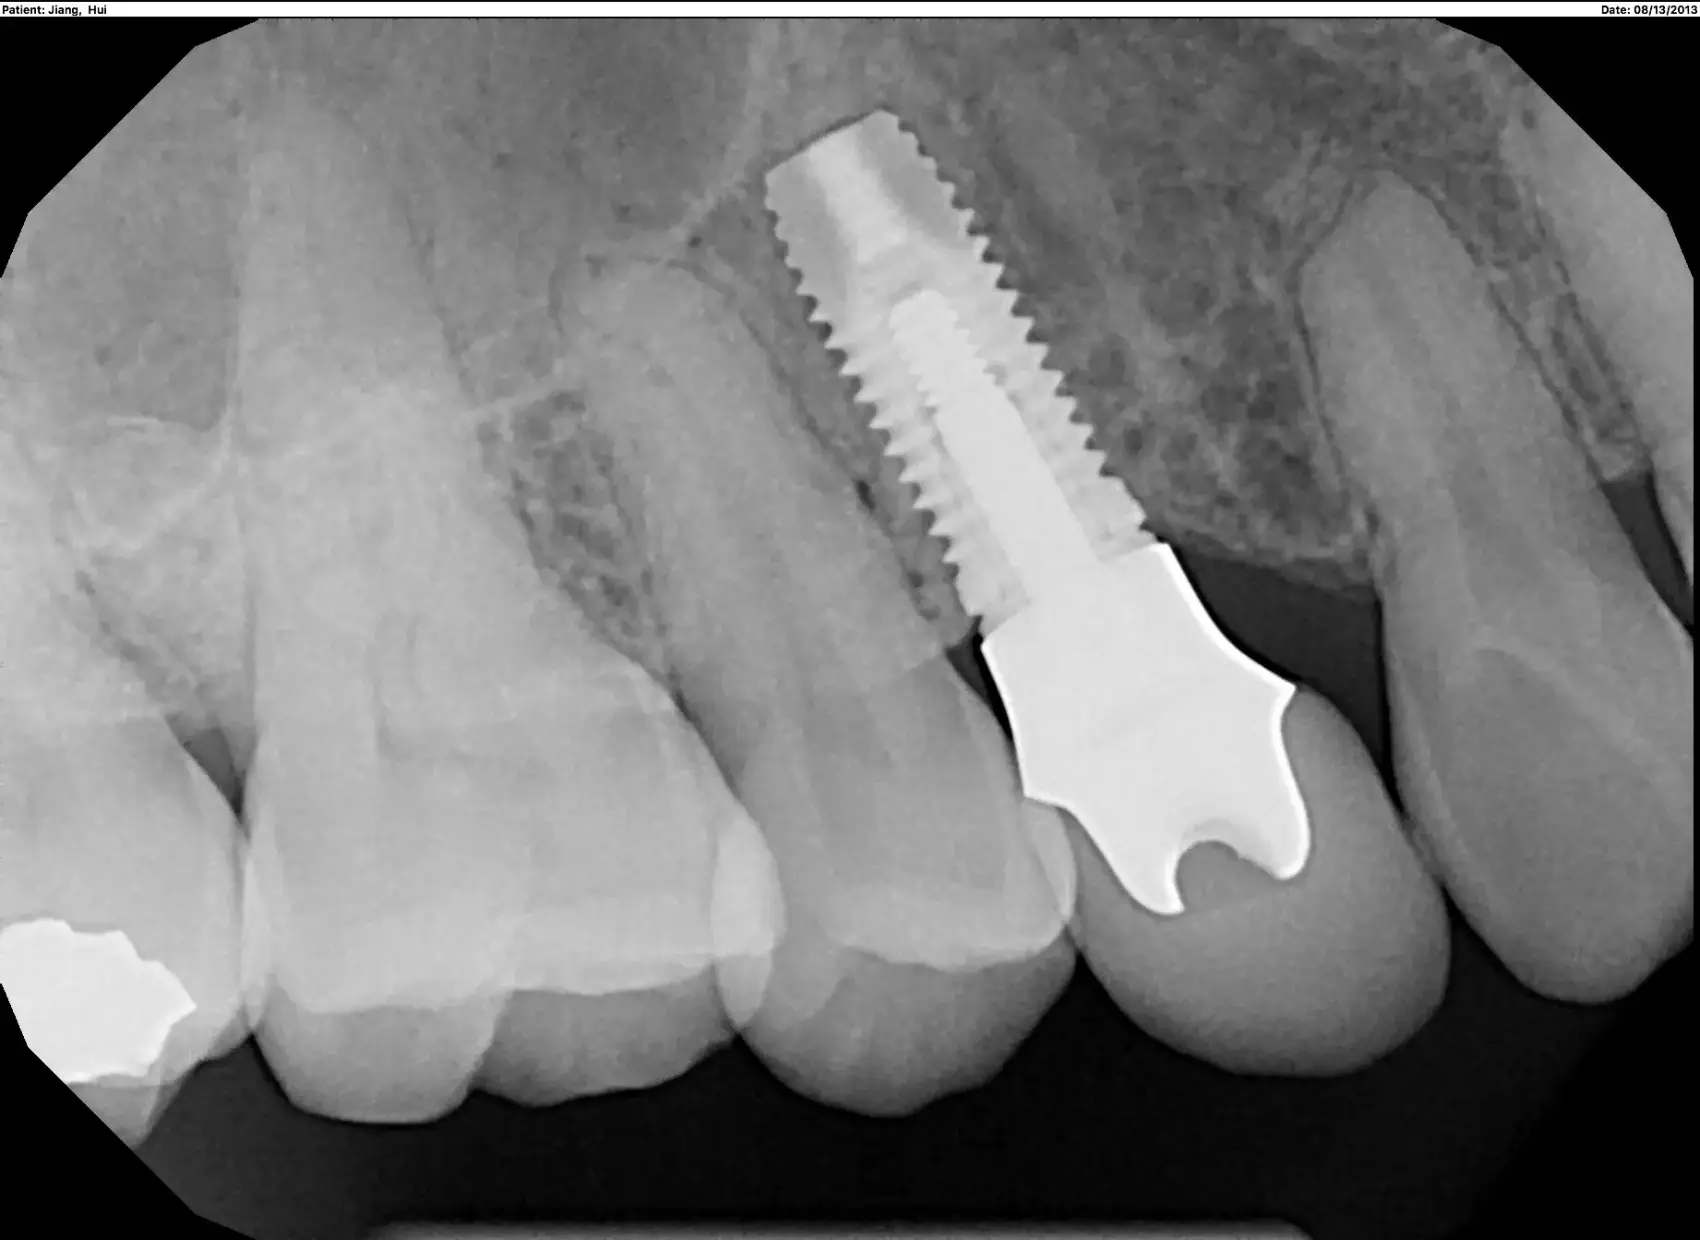

A dental implant consists of a titanium post surgically implanted into the jawbone, functioning like an anchor for a crown attached above the gumline. The implant fuses with the jawbone in a process called osseointegration, a process that can take several months of healing time to complete. Once the jaw has healed around the implant, it can safely support an abutment and dental crown without the risk of drifting out of place. Dental crowns are commonly placed over implants to restore the appearance of lost or damaged teeth. Since implants fuse to the jawbone, they provide increased stability compared to traditional dentures and other methods of tooth replacement.